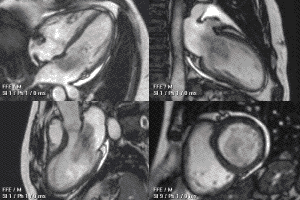

Functional and structural information is acquired using bSSFP cine sequences. These are usually retrospectively-gated and have intrinsically high contrast in cardiac imaging due to the relatively high T2:T1 ratio of blood compared to myocardium. Images are typically planned sequentially to achieve the standard cardiac planes used for assessment. Turbulent flow causes dephasing and signal loss allowing valvular disease to be qualitatively appreciated. The left ventricular short axis cines are acquired from base to apex and are used for quantifying end-diastolic and end-systolic volumes, as well as myocardial mass. Tagging sequences excite a grid pattern that deforms with cardiac contraction allowing strain to be assessed.

Example CMR images. In sequence: a coronal localiser, 2 chamber cine, 4 chamber cine, left ventricular short axis cine, and tagged image. Additional cines of the left ventricular outflow tract and aortic valve may also be acquired.